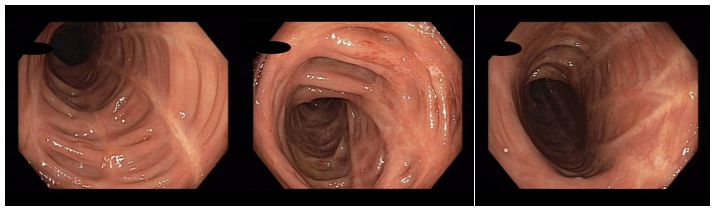

Koloskopie 2022/2: Pozánětlivé změny celého tračníku (jizvy), v rektosigmatu je reziduální ulcerace v centru serpiginózní ulcerace – bez makroskopických známek aktivity v tračníku i terminálním ileu. Vyšetření v bílém světle i NBI